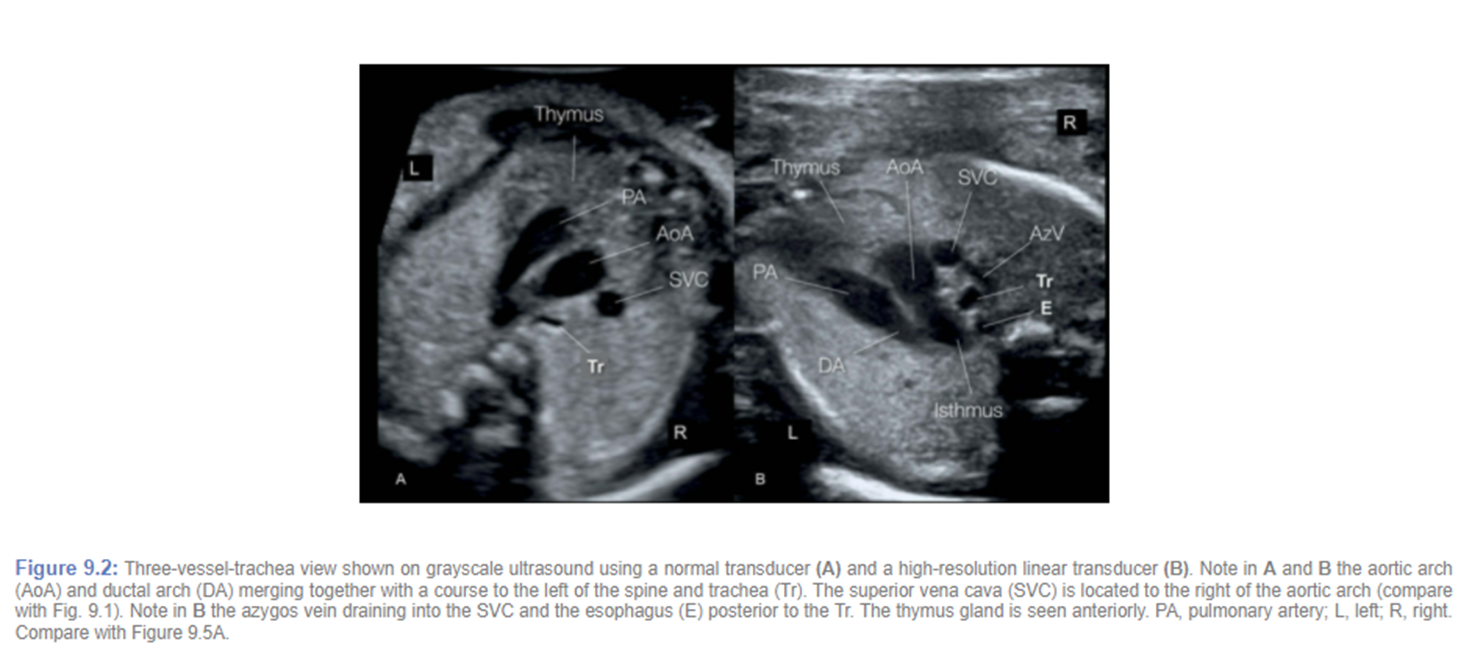

pulmonary artery comes out of ???

right ventricle

pulmonary artery quickly passes _____ and ____ of ascending aorta

anterior and left

right pulmonary artery passes ____ to the aorta

posterior

3 vessel view (3VV)

pulmonary artery and aorta junction

ductus arteriosus

Where pulmonary artery and aorta join (ductus arteriosus) in the 3VT view is sometimes also referred to as the

transverse arches

3vt (thymus)

pulmonary artery vs aorta color flow

same color and flow towards spine

3VV with trachea